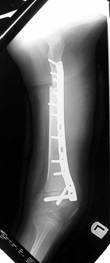

Follow Up

Left tibia lengthening with fixator in place

Lengthening tibia on Xrays in progress

Lengthening proceeding

Converted to immediate exchane nail after 65mm lengthening

Consolidation regenerated